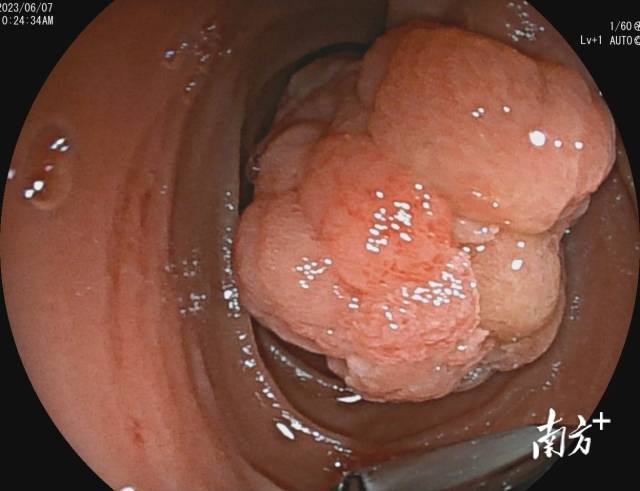

经南方医院消化科电子胃十二指肠镜检查,陈先生被诊断为十二指肠乳头肿瘤,肿瘤大小约5×4cm,几乎占据整个肠腔,使用侧视镜及直视镜均无法窥见肿瘤全貌。但超声内镜评估该肿瘤未侵犯固有肌层,后方胆胰管未见明显累及,根据诊疗指南,医生判断有内镜下微创治疗的可能。

十二指肠乳头腺瘤几乎占据整个肠腔。 受访者供图

患者病变位于十二指肠降部延至肛侧,普通内镜下无法探及病变肛侧,且由于肿瘤巨大,一般牙线及钛夹无法有效牵引如此重的肿物,术中如何牵引并暴露肿物及黏膜下层?对此,罗晓蓓博士设计了暴露牵引病变的策略,使用圈套器在钳道内抓住并牵引病变,通过剪断圈套器把手部位将圈套器反向推出内镜,通过创新性地使用圈套器在镜身外牵引,把肿物向口侧提拉,以暴露肿物基底部,使电刀及内镜可以触及病变,并进行剥离。